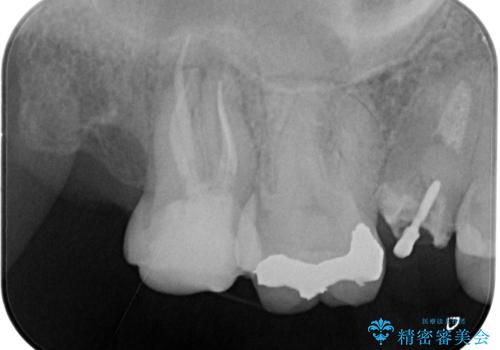

- 左上7番の奥歯に、根尖部の大きな病変を認め来院されました。レントゲンと精密検査の結果、歯の根の先に膿が溜まっている状態と診断。歯を残すことを第一に考え、精密根管治療による改善を目指す治療計画を立案しました。治療においては、細菌の侵入を徹底的に防ぎ、病変部を確実に除去するために、ラバーダムと歯科用顕微鏡を併用することを提案しました。

今回の精密根管治療では、まず治療中に唾液や細菌が入らないようラバーダムで患部を隔離しました。次に、肉眼では見えない根管内部を歯科用顕微鏡で拡大しながら確認。これにより、病変部を正確に特定し、感染源を徹底的に除去することができました。また、健康な歯質を極力残すため、必要以上に歯を削らないよう細心の注意を払って治療を進めました。治療後は、根尖部の病変がきれいになくなり、良好な経過をたどっています。これにより、大切な奥歯を残し、再感染のリスクを抑えることができました。